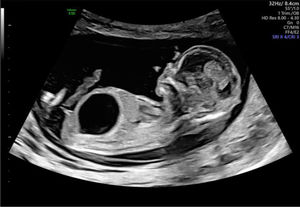

Otro motivo de derivación podría ser la presencia de uno o más quistes renales, cuyo diagnóstico diferencial ecográfico incluye riñón displásico multiquístico (RDMQ), quistes renales simples y riñones poliquísticos. La localización del quiste dentro del riñón, el tamaño renal y el índice de líquido amniótico pueden ayudar a distinguir entre los diagnósticos. El RDMQ se presenta con múltiples quistes, por lo general unilaterales, en la corteza renal, ausencia de pelvis renal y sin parénquima renal normal visible por ecografía (fig. 3). Puede confundirse con hidronefrosis cuando los cálices dilatados simulan quistes grandes; sin embargo, la presencia de parénquima normal y una pelvis renal (dilatada) indica hidronefrosis. Los quistes renales simples pueden aparecer en etapas tempranas de la gestación y la mayoría se resuelven durante el embarazo12.